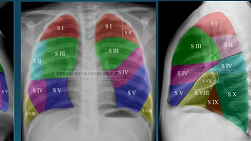

Рентгеноанатомические основы исследования легких. Учение о сегментах. Глава 14

ИСТОРИЯ УЧЕНИЯ О СЕГМЕНТАХ Создателем учения о бронхах и учения о сегментах считается Аэби. Будучи профессором анатомии Бернского университета, он опубликовал в 1880 г. монографию, в которой в сравнительно-анатомическом аспекте обсуждалась бронхиальная система человека, млекопитающих, птиц и рептилий. Многие из его наблюдений не потеряли своего значения и в наше время, но некоторые данные уже устарели. Эго объясняется не только тем, что он располагал лишь незначительным материалом, но скорее...